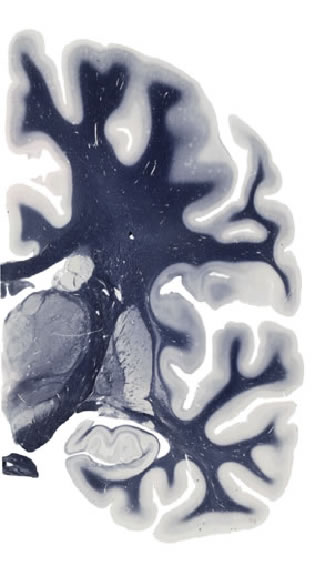

Hi-Resolution Sections · Cells (Nissl Staining) · Virtual Microscopy

Frontal sections (Nissl) from the Atlas Brain: Gallery Slice Single

16,0 mm

Slice ID: r3-0803

Plate NR: ca 34

Position: 16,0 mm